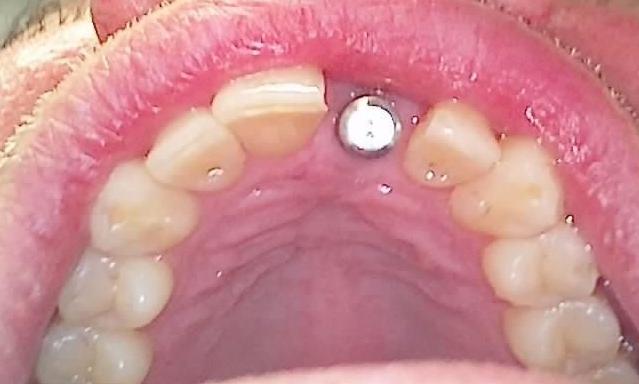

We take great pride in the services we perform in our office. We always try to not only meet your expectations, but we also try to exceed them. There are many types of services that we perform in our office, as well as others that we perform in coordination with highly skilled specialists. We have compiled a few examples of the treatments that we have performed. We are proud to say that these are the usual results our patients expect to see.

The photos are not retouched, nor are they taken by a professional photographer. These are just the routine treatment photos that we take and the results that we see every day. They are by no means a comprehensive catalog of the procedures that we perform. They are just a small sample of some of the results you can expect when you seek treatment in our office.